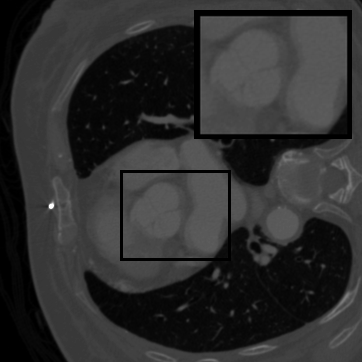

Figure 2: Qualitative inpainting results on TomoBank (lines 1 to 2) and LoDoPaB (lines 3 to 4) with random mask (ratio = 0.8) at 1024×\times1024 resolution. Odd columns and even columns show the sinograms and reconstructed images, respectively.